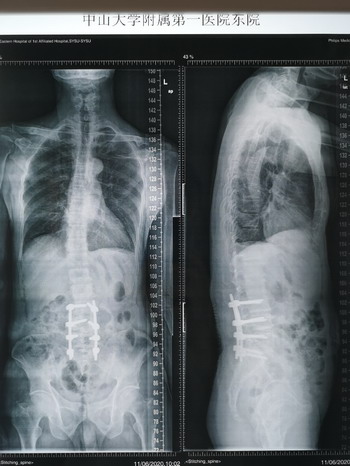

李大爷术后的X光片显示,原本倒向一边的脊柱通过手术已经得到修正,脊柱恢复到正常的曲度。

患者术后X光片

由于手术解除了突出椎间盘对神经的压迫,李大爷原本已经许久无法动弹的左脚术后立即就可以活动。目前,李大爷已经康复出院,费用严格控制在8万2千。他的老年人居民医保报销后自己只需要出一半费用。经过一段时间的恢复锻炼,相信他很快就可以正常行走。